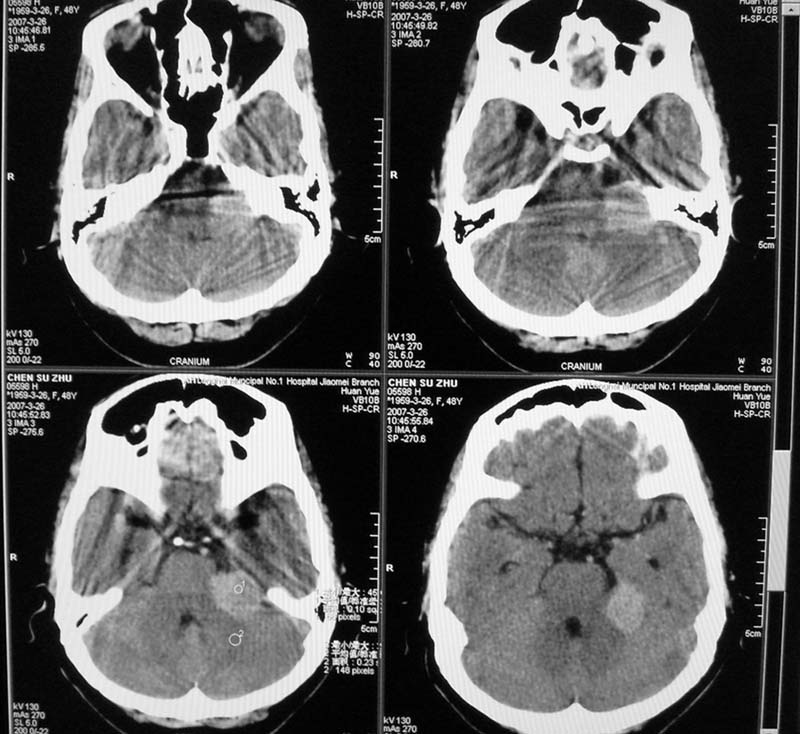

标题: CT8208:女,48岁,反复头晕半年余,无听力、视力障碍 [打印本页]

标题: CT8208:女,48岁,反复头晕半年余,无听力、视力障碍

患者,女,48岁,反复头晕半年余,无听力、视力障碍。病人已手术,结果明天传。

内听道口似未见明显扩大,肿瘤呈类圆形高密度影,考虑脑膜瘤先。

骨窗示内听道未见明显扩大,局部骨质未见明显吸收破坏,

考虑:左侧桥小脑角处脑膜瘤

瘤体与岩骨呈钝角紧密相连。

1.病灶形态规则,密度略高,边界尚清,周围无水肿带,无明显占位效应

2.病人应已强化扫描

左侧桥小脑角区高密度肿块,周围无水肿及明显占位效应,岩骨尖受压吸收,内听道未见扩大,无听力异常,右侧颅骨外板高密度影,边缘锐利,考虑:左侧脑膜瘤,右侧颅骨骨瘤。左侧岩骨尖有破坏,三叉神经瘤待排。